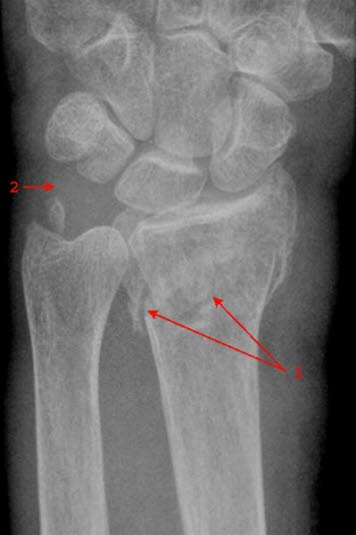

Pasientforberedelser

Ofte står et brudd skjevt slik at beinpipene står skjevt i forhold til hverandre (se figur), ja, noen ganger kan de ha glidd forbi hverandre. Da må legen dra bruddendene fra hverandre før de presses på plass (reponeres). Legen er avhengig av å sammenligne bilder før og etter reposisjonen for å forsikre seg om at bruddet vil kunne gro riktig i den posisjonen det står. I oppfølgingen av et beinbrudd blir det også tatt bilder for å kontrollere at bruddet gror og at det ikke oppstår komplikasjoner av noe slag.